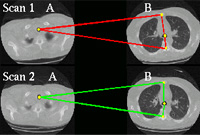

- 在这个持续项目中,我们开发方法对齐医学图像数据集解剖结构注意力集中在胸口结构注册上,如肺面和肺膜结核方法使用僵化变形体变换